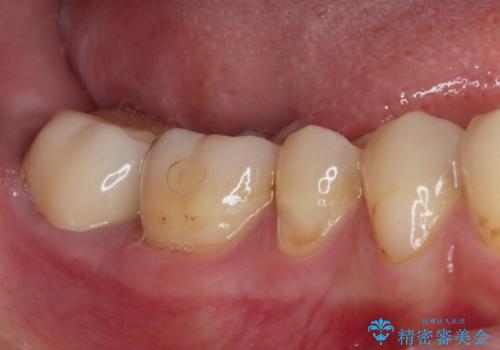

下顎の奥歯は強い痛みを感じており、既に歯髄に不可逆的な炎症が起きていると診断されたため、根管治療の後にセラミッククラウンにて補綴治療を行うこととしました。

上顎の奥歯は最近銀歯による治療を行ったとのことでしたが、適合が不十分であり隙間からしみていたため、適合の良いゴールドインレーにて修復治療を行うこととしました。

下顎のむし歯は歯肉の中にまで及んでいたため、一部歯槽骨を削除し、歯肉縁上に健全歯質が位置するよう外科処置を併用しました。